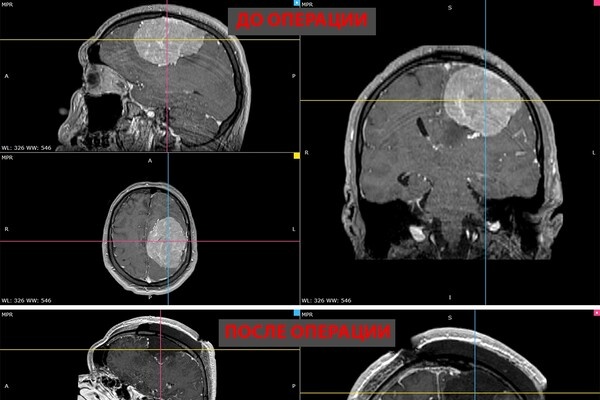

В Новосибирске врачи удалили 35-летнему пациенту гигантскую опухоль головного мозга. Об этом сообщает пресс-служба НМИЦ имени Мешалкина Минздрава России. В ноябре прошлого года у мужчины появилась слабость в правой руке и затруднения речи — МРТ выявила у него менингиому диаметром более восьми сантиметров в левом полушарии мозга. К концу года рука практически перестала работать, ходьба давалась пациенту с трудом. Уже в январе, когда мужчина готовился к плановой операции, у него выявили тромбоэмболию легочной артерии. Из-за высокого риска осложнений в нейрохирургическом лечении ему отказали. Тем временем его симптомы нарастали — появились эпилептические приступы с потерей сознания и судорогами. Семья обращалась в разные клиники, но согласилась принять пациента только НМИЦ Мешалкина, где одновременно занимаются нейрохирургией и лечением тромбоэмболии. «Когда его привезли, он уже был наполовину парализован, приступы стали ежедневными. Ждать было нельзя», — рассказал нейрохирург. Консилиум

В ноябре прошлого года у мужчины появилась слабость в правой руке и затруднения речи — МРТ выявила у него менингиому диаметром более восьми сантиметров в левом полушарии мозга. К концу года рука практически перестала работать, ходьба давалась пациенту с трудом.

Пятичасовая операция прошла успешно. Опухоль удалили полностью. Уже на следующий день появились движения в руке, через две недели пациент снова стал сам ходить. У него восстановились речь и движения, приступы исчезли.